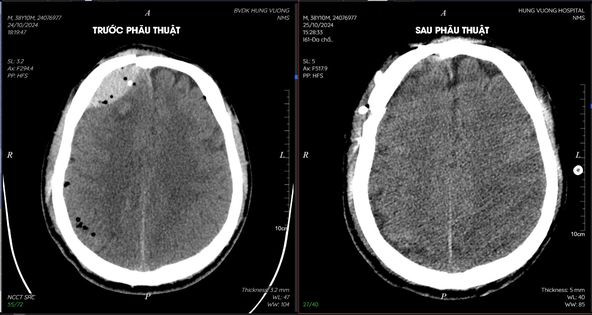

Kết quả chụp CT cho thấy một loạt các chấn thương nghiêm trọng, bao gồm vỡ tầng sọ trước hai bên, tụ máu và khí nội sọ lan tỏa, cùng các tổn thương gãy xương phức tạp vùng hàm mặt.

Ngay lập tức, bệnh nhân được hội chẩn cùng Bác sĩ Sùng Đức Long, Phó khoa Ngoại tổng hợp 2 và chỉ định tiến hành phẫu thuật khẩn cấp: Lấy máu tụ dưới màng cứng, trong não cấp tính - tạo hình tái tạo các tổn thương xương phức tạp vùng hàm mặt.

Sau phẫu thuật và quá trình điều trị hồi sức tích cực, sức khỏe của bệnh nhân đã dần ổn định.